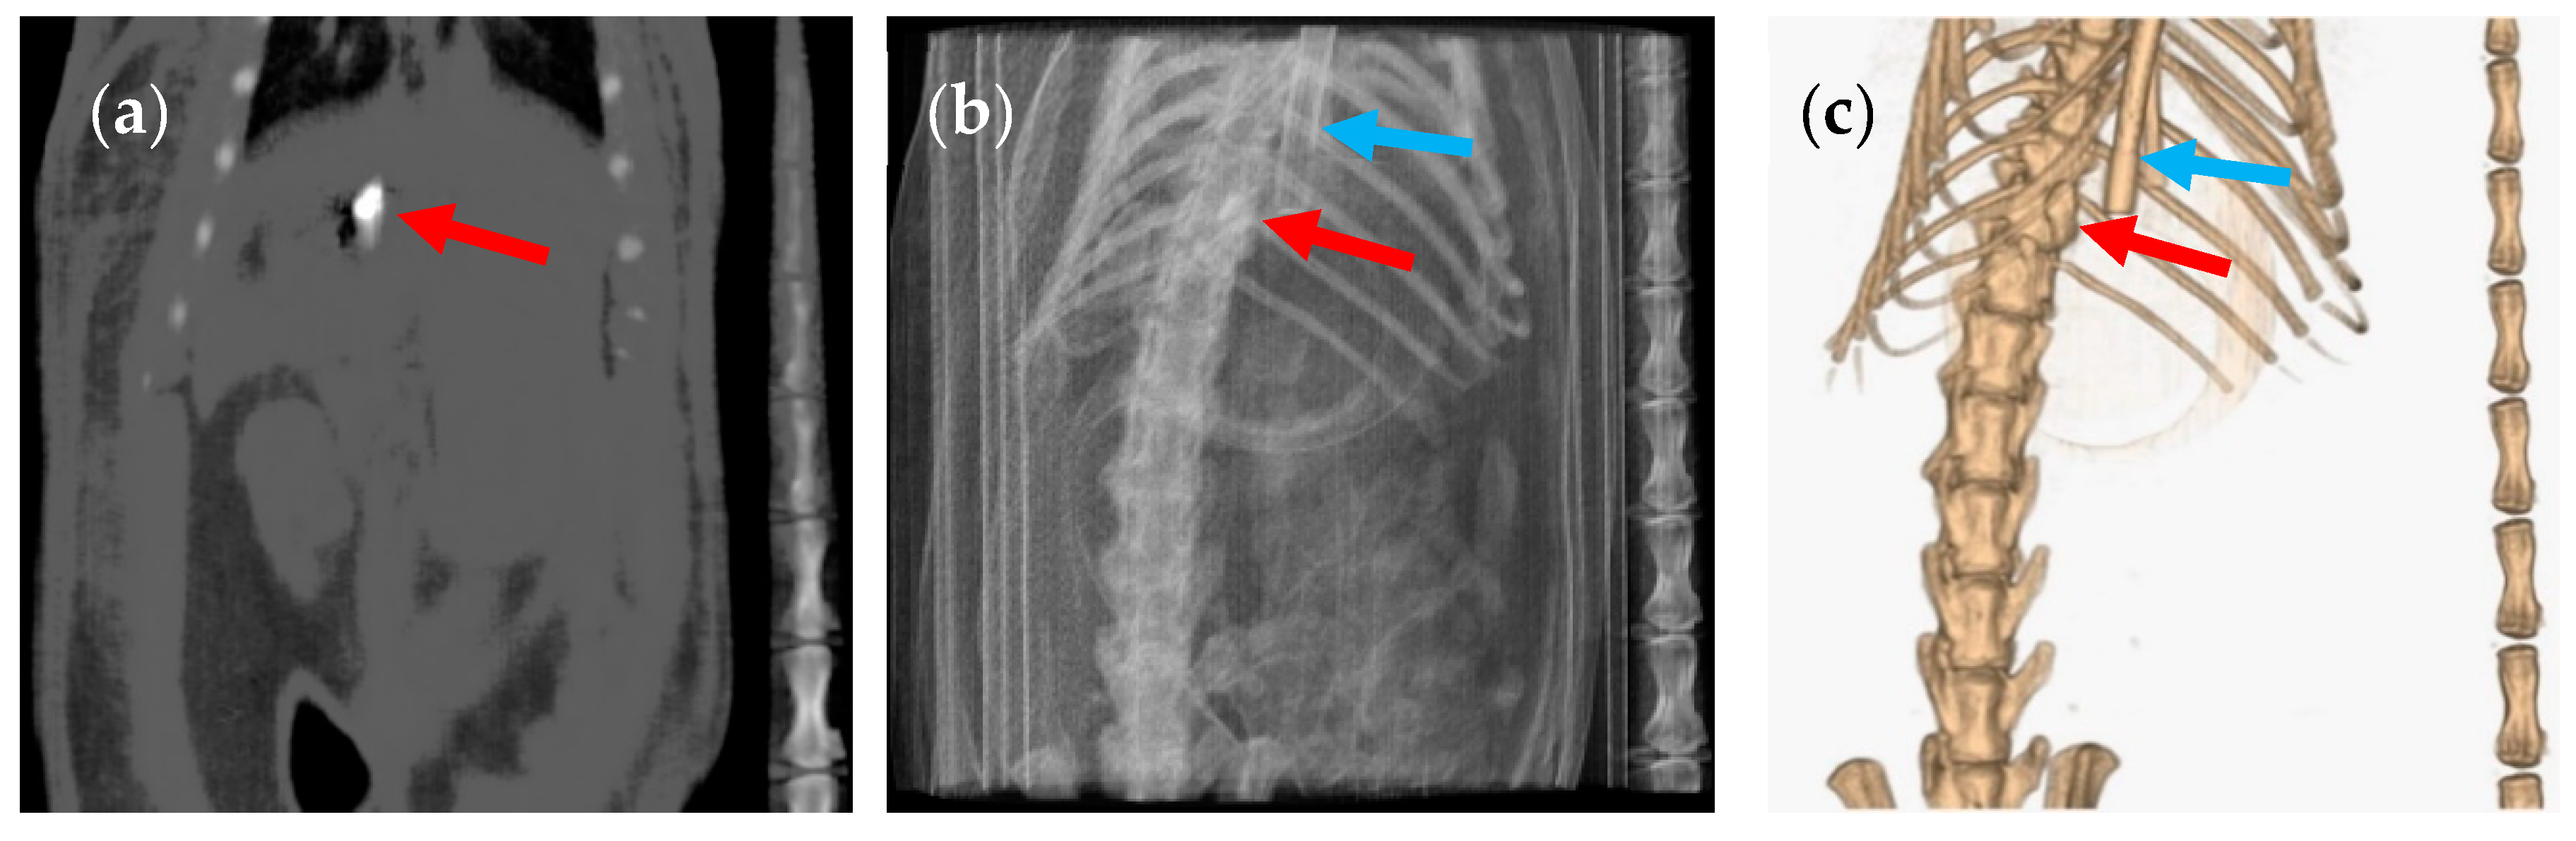

3. Results and Discussion